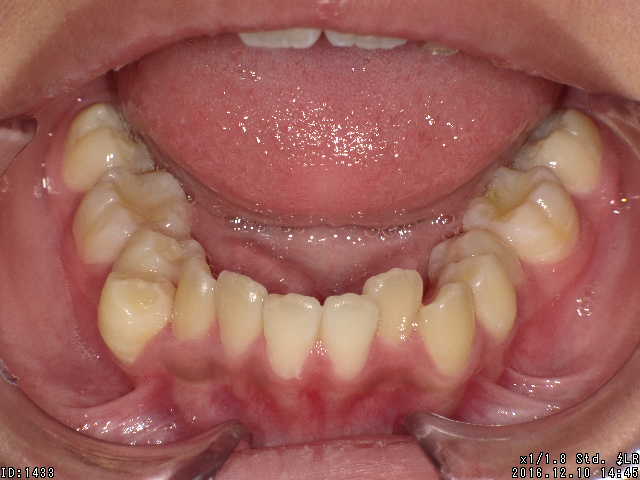

矯正前